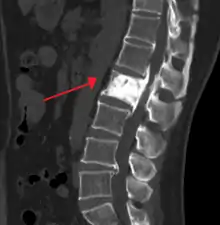

| "This 92 year-old male patient presented for assessment of sudden inability to move half his body. An incidental finding was marked thickening of the calvarium. The diploic space is widened and there are ill-defined sclerotic and lucent areas throughout. The cortex is thickened and irregular. The findings probably correspond to the 'cotton wool spots' seen on plain films in the later stages of Paget’s disease." | |